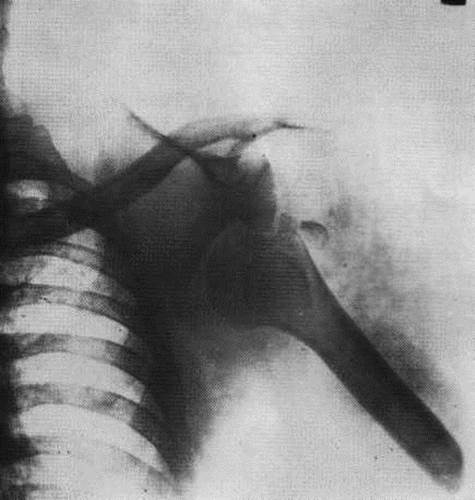

1) Какой сустав изображен на рентгенограмме?

2) Назовите основной признак вывиха и покажите его на рентгенограмме.

1) Плечевой сустав.

2) На рентгенограмме – вывих левого плечевого сустава: полное нарушение соответствия (смещение) суставных концов.